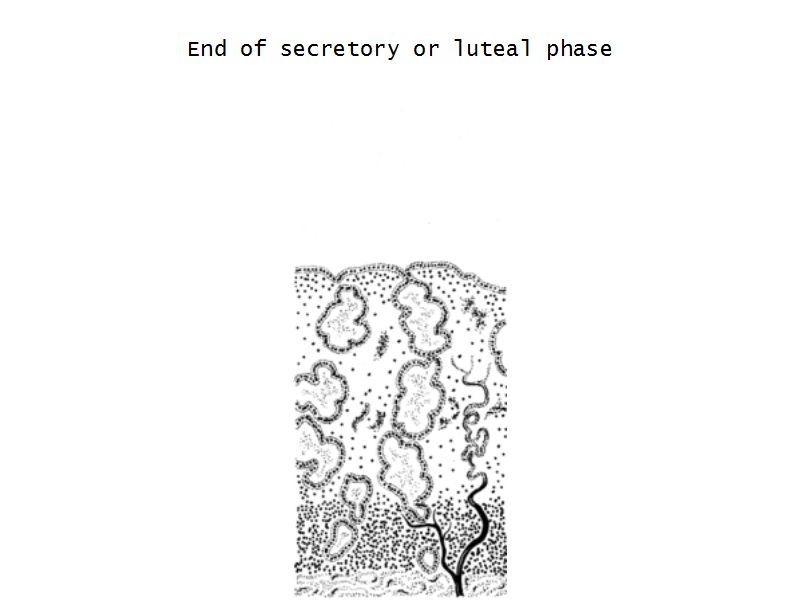

Menstrual cycle

- Follicular phase

- Luteal phase

- Menstrual phase

Luteal phase

- Thickening endometrium

- Edema

- Endometrial gland secretion

- Glands

- Glandular cells at apex

- Basal accumulation glycogen

- Helical arteries reach superficial regions